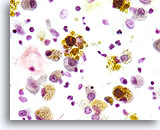

Figure 161

Macrophages

In cases of lipoid, or aspiration pneumonia the macrophages contain multiple complex lipid vacuoles.

Macrophages

In cases of lipoid, or aspiration pneumonia the macrophages contain multiple complex lipid vacuoles.

Figure 161

Macrophages

In cases of lipoid, or aspiration pneumonia the macrophages contain multiple complex lipid vacuoles.

Macrophages

In cases of lipoid, or aspiration pneumonia the macrophages contain multiple complex lipid vacuoles.